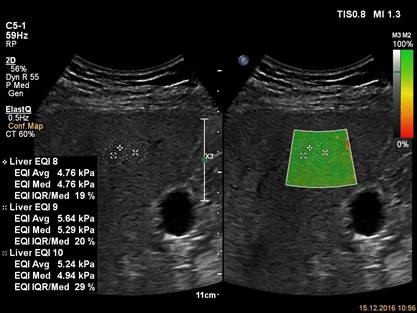

Для исследования используется прибор EPIQ 7, датчик С5-1, приложение ElastQ. Датчик расположен в интеркостальном промежутке, капсула видна как яркая белая линия, перпендикулярно расположенная ультразвуковому лучу. Зона интереса расположена в середине изображения в ткани правой доли печени. В зоне интереса нет крупных сосудов и артефактов. Зона интереса преимущественно окрашена в цвета характерные для эластичной (не жесткой) ткани при выбранной цветовой схеме. Фактор качества исследования (интерквартильный размах/медиана) не превышает 30% для каждого из четырех измерений.

Для исследования используется прибор EPIQ 7, датчик С5-1, приложение ElastQ и карта надежности. Карта надежности исследования позволяет достоверно выбрать участок печени в котором боковые волны имели максимальную интенсивность. Измерение в данном участке печени будет иметь минимальную вариабельность.